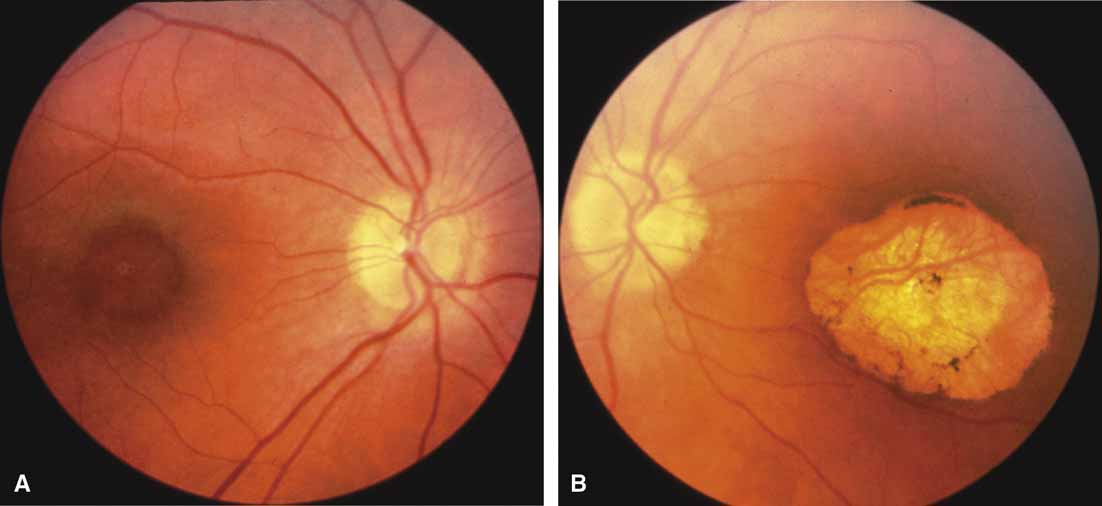

First described by Nettleship12 in 1884, central areolar choroidal dystrophy (CACD) (MIM No. 215500, Phenotype catalog number (MIM) from McKusick VA: Mendelian Inheritance in Man. Catalogs of Human Genes and Genetic Disorders. 12th ed. Baltimore: Johns Hopkins University Press, 1998 [http://www.ncbi.nlm.nih.gov/Omim/]), as it is most appropriately called,13 has been described under many names, including central areolar choroidal sclerosis, central areolar choroidal atrophy, central angiosclerosis, and central senile choroiditis.14,15 The disorder can be autosomal dominant or autosomal recessive, and phenocopies can occur from many other diseases, including mutations of peripherin/RDS16–19 and advanced stages of macular dystrophies (see later text). A locus for CACD has been identified on chromosome 17p.20 The earliest symptoms result from pericentral scotomas and include difficulty reading, poor dark adaptation, reduced visual acuity, and glare sensitivity. The earliest fundus findings are subtle and include pigment epithelial and choriocapillaris lesions in the macula (Fig. 1A) that enlarge and eventually form the punched-out central atrophic lesions typical of this disease (Fig. 1B). Histopathology shows fibrotic scarring with absence of choriocapillaris, retinal pigment epithelium, and overlying photoreceptors in the affected areas.21 The Ganzfeld electroretinogram is usually normal early in the course but may become mildly to moderately abnormal for cone and rod responses late in the course of disease when extensive atrophy of the choroid and secondarily the pigment epithelium and neurosensory retina occurs. Recent studies using the multifocal ERG have indicated that the abnormality of retinal function extends beyond the borders of the visible atrophy and is consistent with presynaptic photoreceptor dysfunction.22 The EOG can be normal or mildly abnormal depending on the extent of associated retinal pigment epithelial dysfunction.

Other forms of central choroidal dystrophy exist that do not show the discrete oval lesions of typical central areolar choroidal sclerosis. These forms of central choroidal choriocapillaris atrophy often present with progressive pigment epithelial mottling and patchy choriocapillaris atrophy initially limited to the macula (Figs. 2A and 2B). With time, the atrophy enlarges and eventually encompasses the entire posterior pole (Fig. 2C). For this form of central choroidal atrophy, a gradual transition usually occurs from atrophic central pigment epithelium and choriocapillaris to essentially normal retina and choroid in the peripheral fundus.